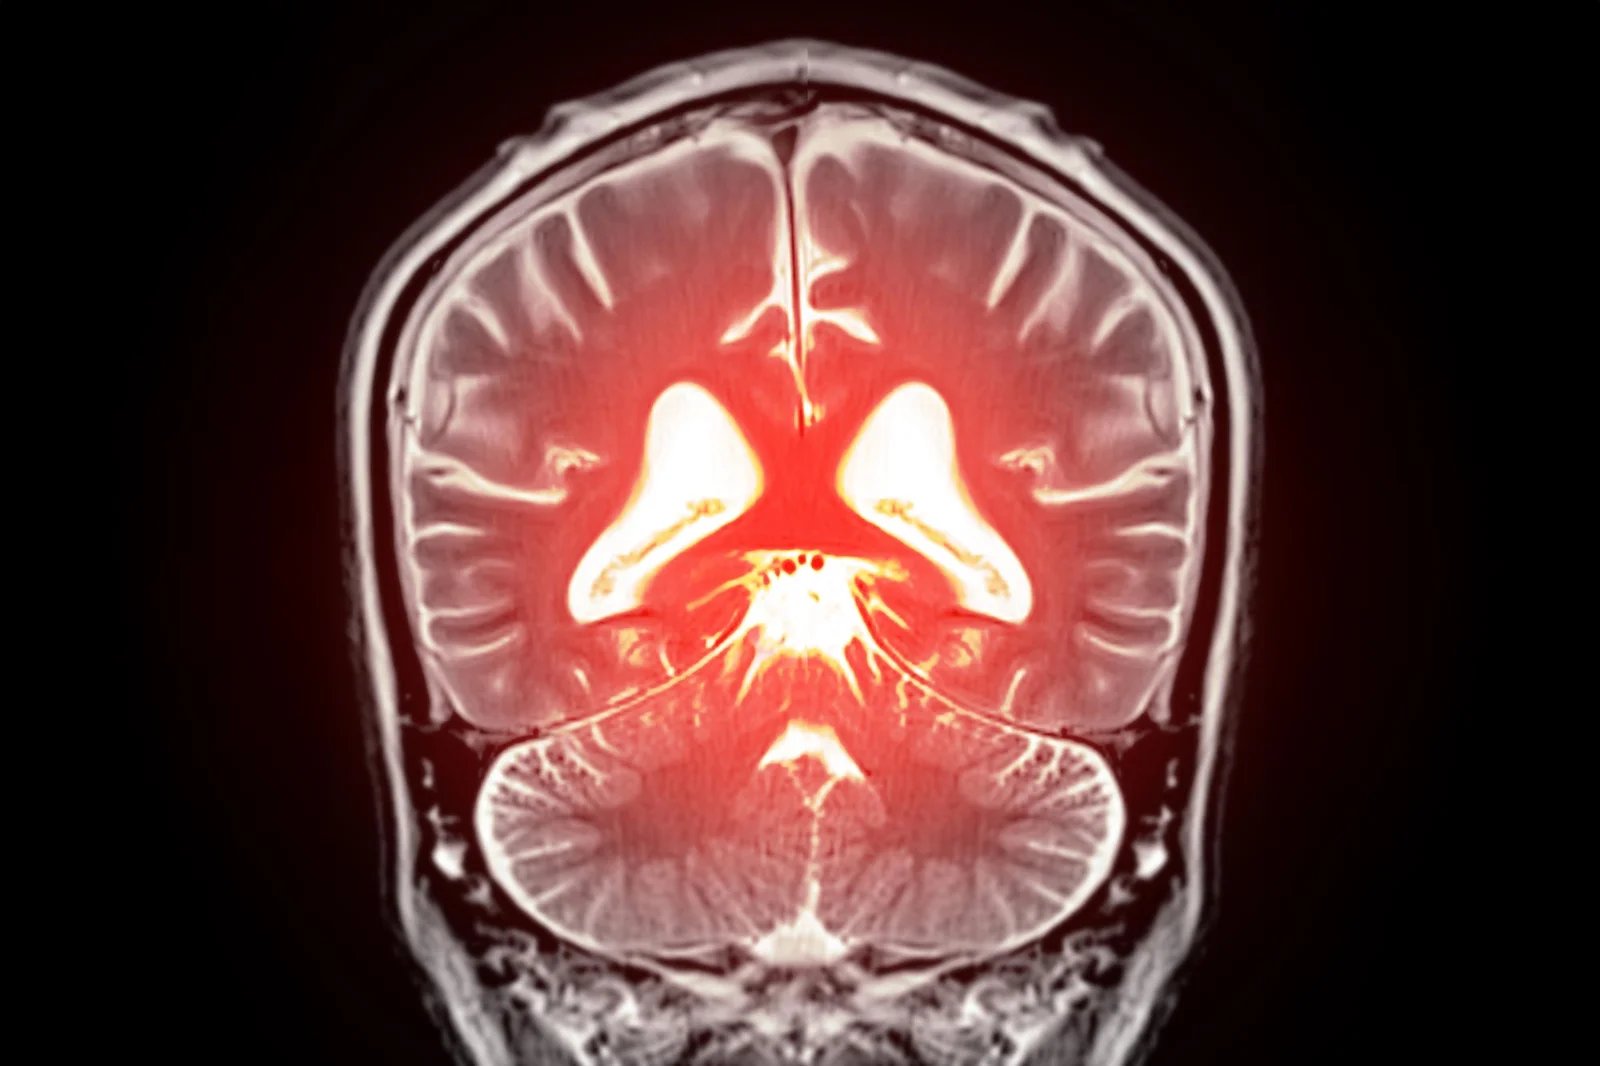

قد يؤدي استبدال الدهون المفقودة في الدماغ إلى تهدئة الأوعية الدموية المفرطة النشاط واستعادة تدفق الدم الصحي، مما يفتح طريقًا جديدًا نحو علاج الخرف.

بدأ يتبلور نهج جديد محتمل لعلاج انخفاض تدفق الدم في الدماغ وبعض أشكال الخرف. كشف علماء في جامعة فيرمونت، روبرت لارنر، دكتوراه في الطب بكلية الطب، تفاصيل جديدة حول كيفية تنظيم تدفق الدم في الدماغ وحددوا استراتيجية يمكن أن تساعد في تصحيح المشاكل في الأوعية الدموية في الدماغ. تم نشر بحثهم قبل السريري اليوم (22 ديسمبر) في وقائع الأكاديمية الوطنية للعلوميشير إلى أن استعادة الفسفوليبيد المفتقد في مجرى الدم قد يساعد في تطبيع تدفق الدم العقلي وتخفيف الأعراض المرتبطة بالخرف.